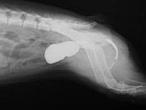

El estudio, que se ha publicado en Reproduction in Domestic Animals, demostró que la uretra finalizaba directamente en la vejiga, y que el clítoris, de 0,8 centímetros de longitud, contenía hueso peneano , lo que predisponía a infecciones de orina y cursaba con infertilidad para el perro.

La perrita Tana, de tres meses de edad en su primera consulta, presentaba un diagnóstico compatible con una alteración genética del aparato reproductor: tenía un clítoris de gran tamaño . “Era una hembra cromosómicamente XX pero con gónadas masculinas (testículos criptórquidos) debido a la presencia de otros genes que determinan la formación testicular en ausencia de los genes presentes en el cromosoma Y”, detalla Campos.